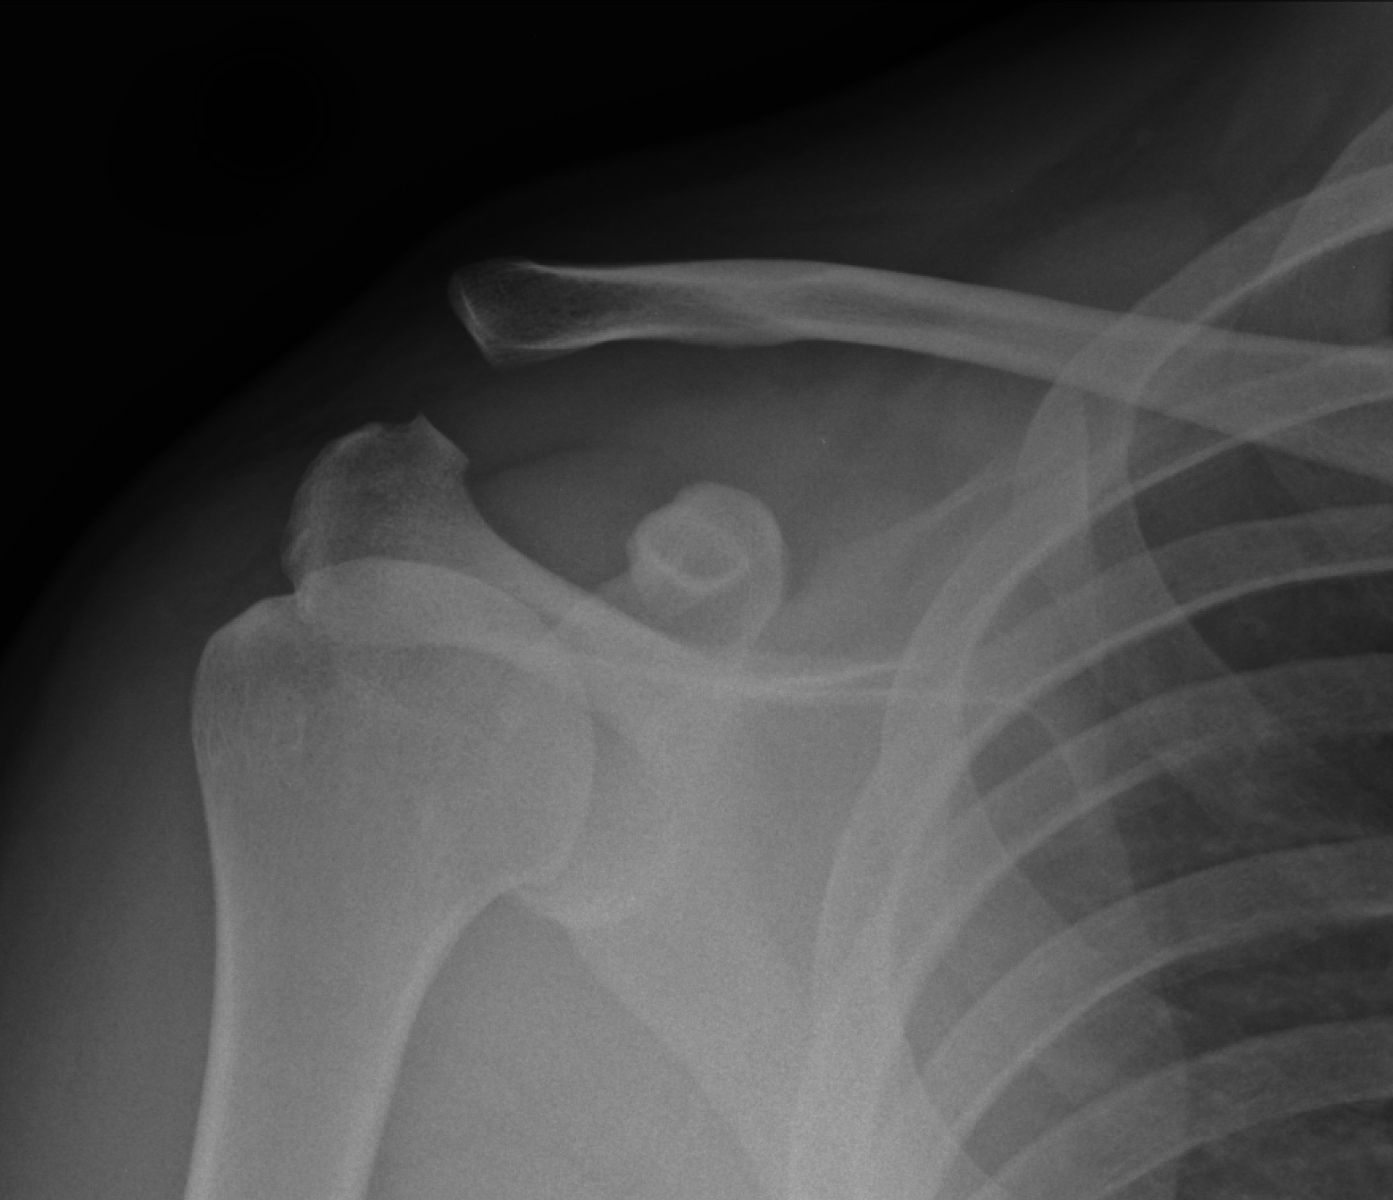

From radiologypics.com